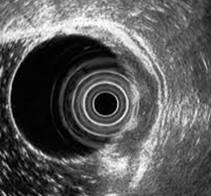

Compromiso del intestino grueso o colitis isquémica: la causa más común es por shock hipovolémico (Ej,. en politraumatizados o gran quemados). Generalmente ocurre a nivel del colon izquierdo (colon descendente y ángulo esplénico). El paciente suele referir dolor en flanco izquierdo asociado con signos de shock hipovolémico. El diagnóstico es por colonoscopia. Eventos crónicos:

Figura 31. Colonoscopia. Se puede observar una mucosa pálida y una pérdida del patrón vascular. Estos hallazgos son compatibles con la colitis isquémica.